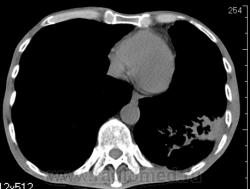

КТ - ОГК.  Ваше мнение коллеги?

На фоне консолидации полость без содержимого. Может быть всё что угодно, что сопровождается деструкцией. Нужны ещё томограммы в лёгочном окне.

Изображения выставлены все. Ваше мнение уважаемые коллеги?

Это КТ 2-летней давности и попало оно мне в руки, после недавнего прохождения контроля пациентом, когда мы стали перед вопросом о специфическом / не специфическом процессе.

Тогда, пациента 2 месяца лечили от пневмонии, лечили интенсивности, стационарно, в серьёзном учреждении.

Предположу аспергиллез